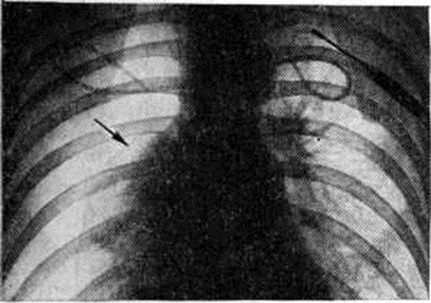

Для рентгенологического выявления пневмоторакса и его характера применяется многоосевое или полипозиционное исследование (смотри полный свод знаний). Рентгеноскопия грудной клетки в прямой проекции даёт ориентировочное представление о наличии Пневмоторакс и его характере и определяет выбор дополнительных методов исследования. Основным рентгенологическое признаком Пневмоторакс любой этиологии является участок просветления, лишённый лёгочного рисунка, расположенный по периферии лёгочного поля и отделённый от спавшегося лёгкого чёткой границей, соответствующей изображению висцеральной плевры (рисунок 1). При рентгенологическое исследовании выявляется связь плевральной полости с окружающей средой. Открытый травматический Пневмоторакс на вдохе характеризуется увеличением газового пузыря, дальнейшим спадением лёгкого, смещением органов средостения в здоровую сторону, смещением купола диафрагмы книзу. При закрытом травматическом Пневмоторакс рентгенологическое картина зависит главным образом от количества воздуха, скопившегося в плевральной полости, и связанного с этим внутриплеврального давления. Различают три типа закрытого Пневмоторакс: с давлением ниже атмосферного, выше и равным ему. При давлении ниже атмосферного количество воздуха в плевральной полости невелико. Лёгкое коллабировано незначительно, на вдохе оно увеличивается в объёме, на выдохе — спадается. При давлении выше атмосферного лёгкое резко коллабировано, его дыхательные экскурсии едва заметны, органы средостения смещены в здоровую сторону, диафрагма смещена книзу. Если давление при закрытом Пневмоторакс равно атмосферному, лёгкое коллабировано частично, дыхательные экскурсии сохранены, средостение смещено незначительно.

При клапанном (вентильном) Пневмоторакс спавшееся лёгкое не меняет своих размеров и конфигурации при дыхании, степень спадения лёгкого максимальная, средостение резко смещено в здоровую сторону, а на вдохе несколько перемещается в сторону поражения. Длительное нагнетание воздуха в плевральную полость при клапанном Пневмоторакс приводит к образованию напряжённого Пневмоторакс; при этом обнаруживается резкое смещение средостения в противоположную половину грудной клетки, диафрагма расположена низко, уплощена. Нередко определяется газ в мягких тканях грудной стенки. При тотальном Пневмоторакс газ занимает всю плевральную полость, тень средостения смещается в здоровую сторону (рисунок 2), купол диафрагмы опускается книзу.